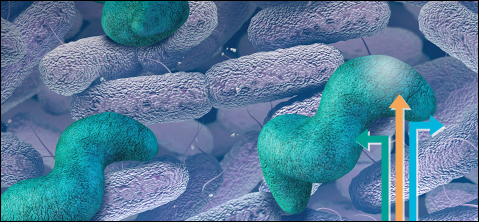

Кампилобактер фетус: патогенез и инфекции